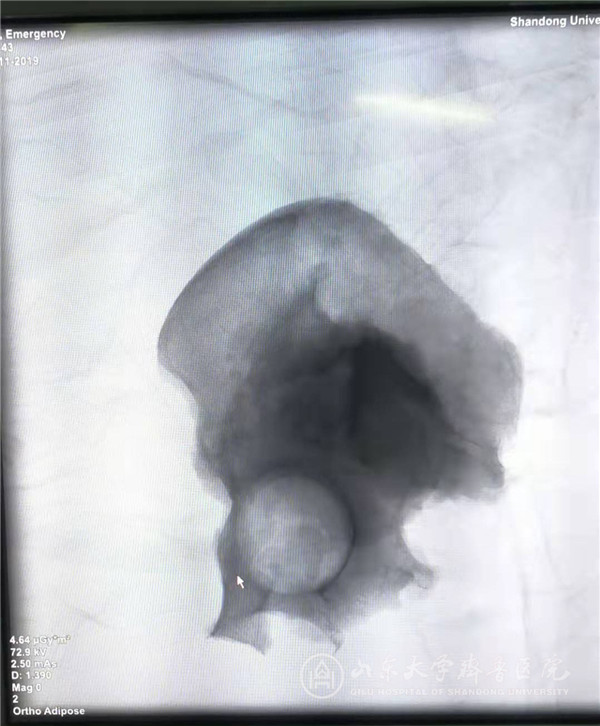

切除的左侧半骨盆透视影像

11月7日18点,手术历时8小时,切除了左侧半骨盆及肿瘤,放置了半骨盆假体,置换了左侧髋关节,增加了腰椎固定。术中虽然放置了髂总动脉阻断带,但因患者动脉钙化明显,术中并未实施阻断,术中出血约4000ml,输入自体红细胞8个单位和异体红细胞8个单位,自体全血400ml,在麻醉医师和医护人员的紧密配合下,手术过程平稳有序,顺利完成。